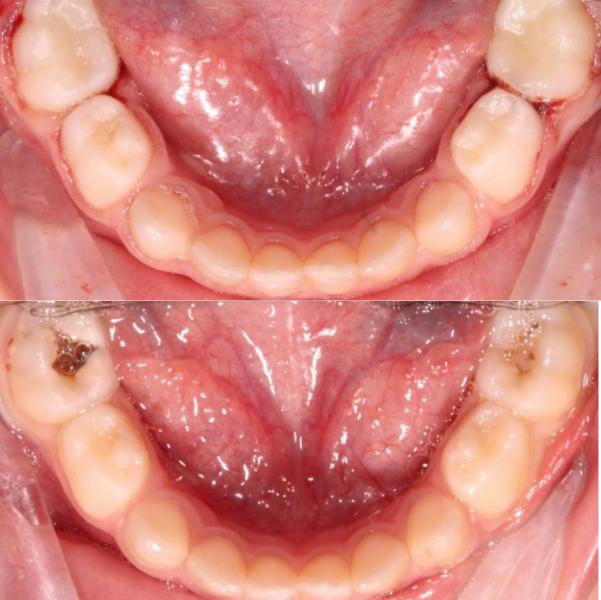

Пролечила 5-х детей в условиях медикаментозного сна, приняла около 10 ортодонтических консультаций

В общем пролечено за сегодня около 40 зубов 🐥